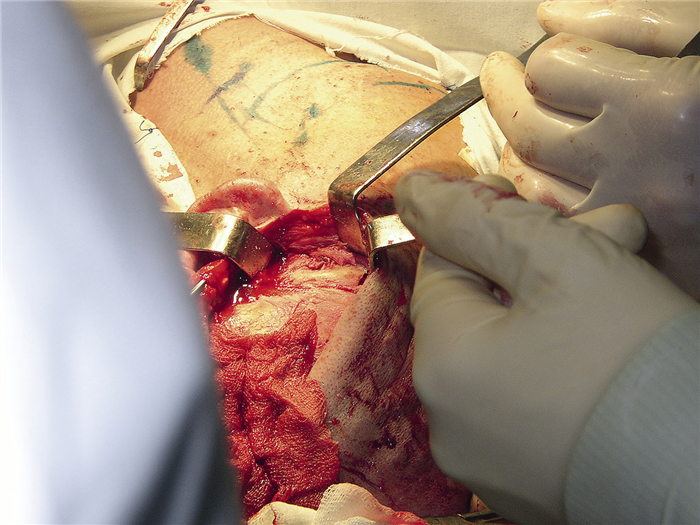

23.03.2004 пациенту проведена операция: удаление новообразования мыщелкового отростка нижней челюсти под эндотрахеальным наркозом с интубацией через нос. Для этого предушным и полувенечным доступом был обеспечен подход к скуловой дуге, которая была затем резецирована и смещена вниз на волокнах жевательной мышцы (рис. 4).

Рис. 4. Операционная рана, венечный доступ, остеотомия скуловой дуги: 1 — скуловая дуга, 2 — области остеотомий.

Волокна височной мышцы были частично пересечены и отслоены, за счет чего выполнен доступ к подвисочной ямке, где спереди и медиально от головки челюсти визуализировалось костное новообразование (рис. 5).

Рис. 5. Область подвисочной ямки, создан доступ к новообразованию.

Опухоль отделена от мягких тканей и фиксирована с помощью специального костного фиксатора, выполненного в виде штопора (рис. 6).